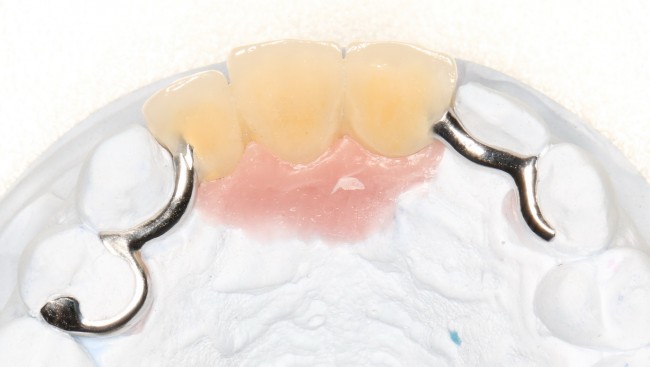

В таких случаях пациенту нередко предлагается какая-то съемная протетическая конструкция (в народе называемая «бабочкой» или «жучком»), задача которой — замаскировать отсутствие зуба до его восстановления с помощью импланта:

И, я должен заметить, что с маскировкой такой простейший протез отлично справляется:

либо лабораторно изготовленный временный протез с опорой на соседние зубы: